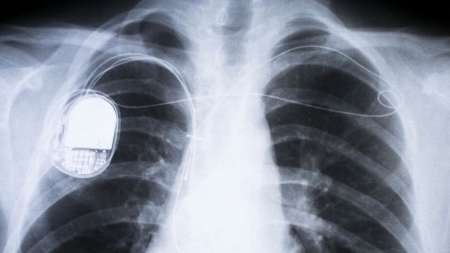

آیا ضربانسازها هک می شوند

آیا ضربانسازها هک می شوند سازمان غذا و داروی آمریکا خط مشیهایی را منتشر کرد که سازندگان دستگاه ضربانساز را در جلوگیری از حمله هکرها به ایمپلنتهای ضربانساز که با استفاده از شبکههای ابری کار میکنند، یاری میکند.این خط مشیها خطاب به سازندگان دستگاههای ضربانساز، دیفیبریلاتورها و پمپهای انسولین که دائما این دستگاه ها را با نرمافزارهای جدید بهروز رسانی …